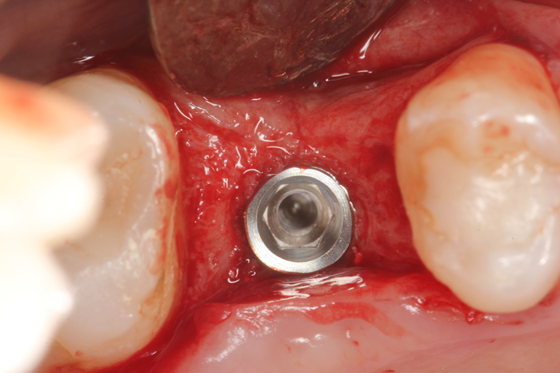

Paciente C.B.F.J., 33 anos, leucoderma, não-fumante e em boas condições de saúde sistêmica, relatou sensibilidade dolorosa durante mastigação no elemento 26, que já possuía tratamento endodôntico, pinos metálicos intrarradiculares e coroa metalocerâmica (Figura 1). Foi solicitada tomografia computadorizada de feixe cônico, na qual a imagem sugeriu fratura radicular na região da furca, descontinuidade óssea da cortical de seio maxilar e opacificação parcial do seio maxilar esquerdo (Figura 2). Foi realizada a exodontia e pôde-se confirmar a comunicação oroantral (Figura 3). Após curetagem do alvéolo, sem preocupação em curetar e remover a lesão cística sinusal, uma barreira reabsorvível foi recortada e posicionada no fundo do alvéolo para obliterar a descontinuidade óssea e impedir que células de tecido mole oriundas da cavidade sinusal invadissem a região alveolar (Figura 4). O alvéolo foi preenchido totalmente por coágulo sanguíneo do paciente (Figura 5) e o alvéolo foi selado por uma barreira não-reabsorvível (Figura 6), impedindo a invasão de fibroblastos do tecido gengival para dentro do alvéolo. Após duas semanas, a barreira estava estável e, então, foi removida, desnudando um tecido de granulação osteoblastogênico (Figura 7).